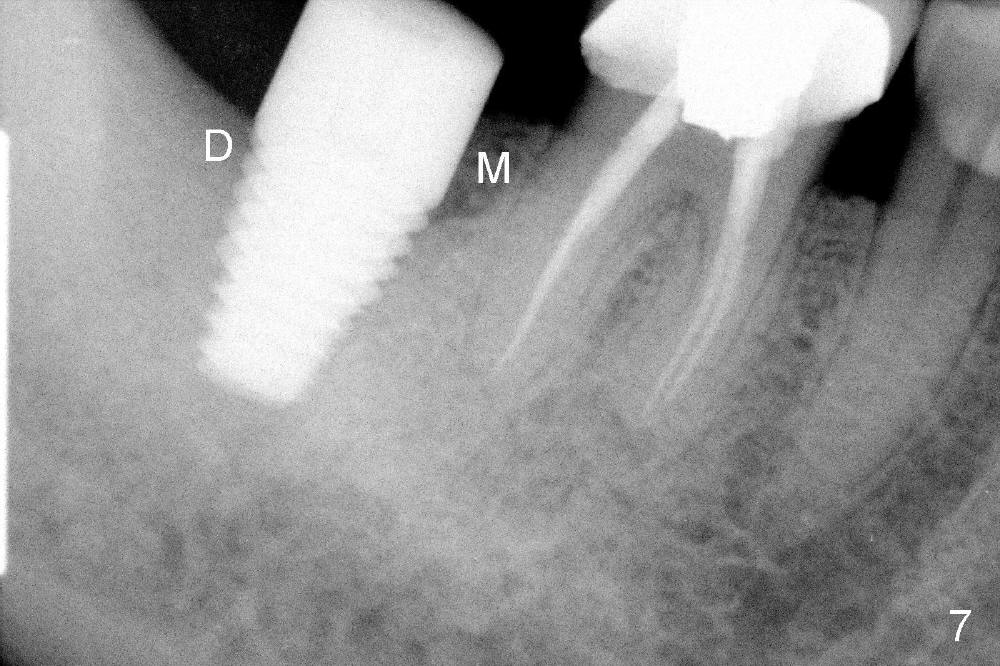

A 62-year-old lady has an advanced endo-perio disease associated with the tooth #31 (Fig.1). IAN is not distinct in the preop PA. IAN is assumed far away from implant area. The implant is planned to be placed along the long axis of the tooth for the best restorative result (Fig.2). The tissue-level implant is placed ~ 3 mm above the distal crest so that implant threads may be less likely exposed postop. Is it a good treatment plan?

No. First at all, CT should be taken when 2D image does not show IAN. Fortunately, the surgery happens to be executed better than the plan. Clindamycin is used for socket soaking for 5 minutes. The initial osteotomy should be not exceeded 6 mm from the distal surface of the first molar (Fig.3: 5.92 mm). The 2 mm pilot drill (D) penetrates the mesial slope of the socket (red line) for 3-4 mm. There is 2.72 mm from IAN (yellow line: upper border of IAN canal). If the implant is placed along the long axis of the tooth, the initial osteotomy should start at the apex of the socket. The same pilot drill (black outline) penetrates the nascent bone for the same distance (3-4 mm) for primary stability, IAN may be invaded! The patient is a severe gagger. She manages to allow us to take this PA (Fig.3) and the next one (Fig.4 with 6x14 mm tap in place, primary stability having been achieved). To close the socket, a 7x14 mm implant is placed. Immediately postop PA is taken twice without success. The socket is closed with 2 sutures and heals around the implant 8 days postop (Fig.5,6). PA is taken 2 months postop (Fig.7). The implant is not placed as deep as planned. It is stable without paresthesia of the lower lip. An abutment is placed (Fig.8: A) nearly 3.5 months postop.